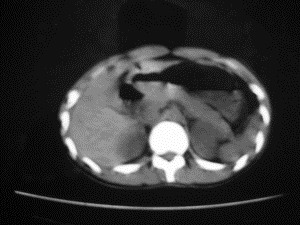

患者女,20岁,被车撞伤3小时,pe:全腹肌紧张,压痛反跳痛,以右上腹为著,肠鸣音减弱。有手术结果。![]() ![]() ![]() ![]() ![]() ![]() ![]() ![]() ![]() ![]() ![]() ![]() ![]() ![]() ![]() ![]() ![]() ![]() ![]() ![]() ![]() jiajie发言: ![]() 考虑空腔脏器穿孔。 dyqct发言:考虑:1、肝左叶外侧段断裂伤伴少量腹血。2、空腔脏器穿孔。 fangzheng发言:仅见腹腔内游离气体,提示空腔脏器穿孔。 guoke发言:胃内密度增高,肠腔内充满气体,考虑肠腔破裂出血 mmg94发言:胃后壁见一增厚软组织密度影,肝左叶前见游离气体影,左腹腔内局部肠管壁、系膜增厚。并见类圆形软组织。以上征象提示消化道管腔破裂,小肠、肠系膜挫裂伤,腹腔血肿形成。 拾荒者发言:肝实质密度不均匀,胃内见不均匀高密度影。考虑:肝挫裂伤,胃内应激性溃疡出血。 守望可可西里发言: 以下是引用jiajie在2006-6-20 15:49:00的发言:[br] [br][br]考虑空腔脏器穿孔。jiajie老师,我鼓起了很大的勇气才决定给您唱个反调儿,如果我错了,请您一定给我指出来,谢谢您了。我反复看了解剖图谱,觉得您所说的“考虑空腔脏器穿孔”上图所用箭头标明的不是游离气体。请您看以下几幅图片: ![]() ![]() ![]() ![]() ![]() ![]() ![]() ![]() 再请您看向医生老师发表的解剖图谱3幅 ![]() ![]() ![]() 这以下几幅图,我认为是肝包膜下积血。不过,说实在话,我没有发现有明显的肝挫裂伤。不对的地方请您一定指出来,再次感谢您了,jiajie 老师! ![]() ![]() ![]() ![]() 这下面几幅图片,我认为有明显的左中上腹部小肠损伤。 ![]() ![]() ![]() ![]() ![]() ![]() ![]() ![]() jiajie 老师,估计我说的是错误的,但我实在闹不明白,请您一定不要笑话我,并指出我的错误,以便于我减少工作中的失误。再次感谢您了,jiajie 老师! 至于胃内的不均匀高密度,我认为拾荒者战友说的有道理,胃内应激性溃疡出血和胃内容物混合所致。 手术结果:左肝叶(iv段)前缘长约8cm挫裂伤口,舌叶根部下< |